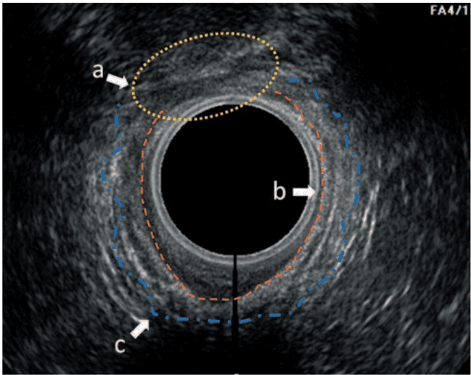

Echo-Assisted Intersphincteric Autologous Microfragmented Adipose Tissue Injection to Control Fecal Incontinence in Children

Giovanni Parente, Valentina Pinto, Marco Pignatti, Neil Di Salvo, Simone D'Antonio, Michele Libri, Mario Lima, 2022